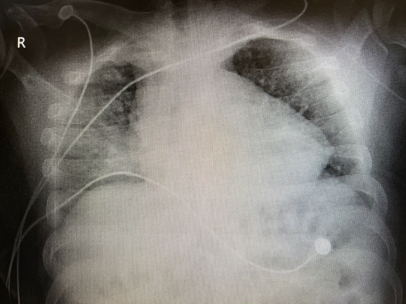

后续检查及预后

通过气管镜肺泡灌洗发现气道远端大量血性分泌物。考虑对于长期心衰患者,在合并感染情况下,血性分泌物淤积在远端小气道或肺泡腔内,改善湿化以后,可能使这些淤积的分泌物被“泡开”,使氧后变得更差。插管吸痰及造影后拔管,复查患者胸片可见明显好转。

所以,对于无创通气患者,一定要关注其分泌物情况,避免发生痰堵。

图片